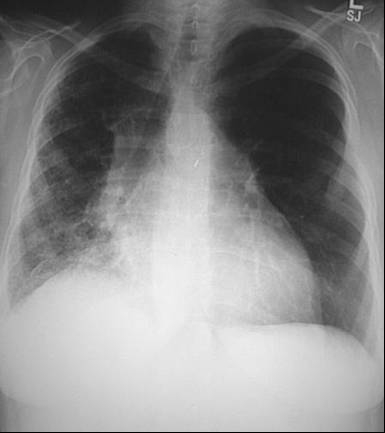

Radiografia toracica

Semnele radiologice. Cordul este marit de volum: diametrul bazal cardiac este mai mare decat jumatatea diametrului transvers bazal pulmonar. Venele pulmonare sunt dilatate. Artera pulmonara principala dreapta este dilatata si ea, la fel si ramura stanga a arterei.

Campurile pulmonare sunt incetosate datorita edemului pulmonar; aceasta tine de mai multe cauze:

• cresterea densitatii interstitiului din zonele centrale pulmonare;

• cresterea densitatii septurilor interlobare, interlobulare si subpleurale (prin aceste zone se face drenajul lichidului transsudat). Acumularea de lichid in spatiile interlobulare produce doua aspecte deosebite, care pot coexista: aspect de linii A. Kerley si de linii B. Kerley, orientate orizontal in zona bazelor; de asemena se constata prezenta de lichid subpleural, de obicei in unghiul costofrenic si bazal, simuland radiologic diafragme ridicate; prezenta de lichid liber in cavitatile mari pleurale (in dreapta in special);

• edemul pulmonar alveolar. Aspectul este "in pete" cu contururi rotunjite; cand conflueaza mai mult zone cu edem, aspectul simuleaza pneumonia, bronhopneumonia, tumoarea sau infarctul pulmonar. O forma mai severa ca prognostic este cea "in fluture";

• mediastinul este rigid;

• venele cava superioara si azygos sunt dilatate.

Examenul obiectiv evidenteaza: facies buhait, rinofima, conjuctive injectate; aparat respirator: raluri crepitante bazal drept; aparat CV - TA 150/90 mmHg, puls 160/min, soc apexian in spatiul VI intercosal stang, aria matitatii cardiace global marita, zgomote cardiace aritmice, zgomotul III prezent, suflu holosistolic de grad II la apex.

Examenul radiologic toracic si electrocardiograma pacientului sunt evidentiate

astfel:.

4. Staza pulmonara (raluri crepitante, diminuarea transparentei bazelor pulmonare, preponderent in dreapta pe radigrafia toracica - edem alveolar) secundara insuficientei ventricului stang (zgomot III prezent).